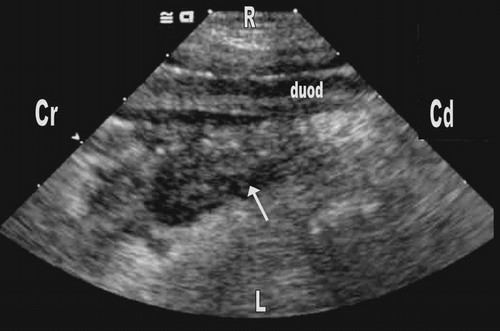

- Ультразвуковое исследование (УЗИ): помогает выявить изменения в прилегающих органах, например, признаки воспаления в поджелудочной железе.